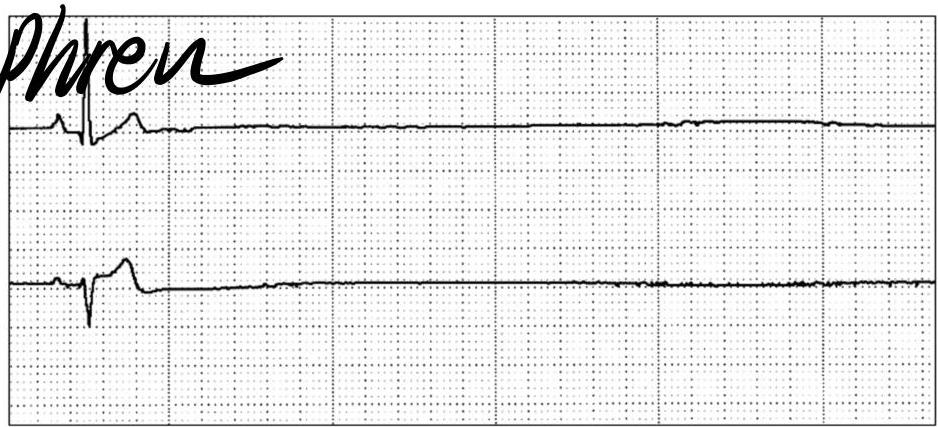

Supraventricular Tachycardia (SVT)

A 1 year old child is brought to the ER because his parents thought his heart was pounding as they were putting him to bed. EKG was done in ER.

Diagnosis? Supraventricular tachycardia (SVT).

Findings:

- Abnormal P waves

- Narrow QRS complex

- Small T waves

- ↑ HR

Causes?

- WPW syndrome

- Ectopic focus / conduction abnormality

ECG Details:

- Narrow QRS complex, HR ~280 bpm, regular RR interval, absent or unclear P-waves

Management (child alert, normal BP)?

- Vagal maneuvers (first step if stable)

- B. Adenosine IV (first line medication if stable)

- Maintenance therapy: Beta-blockers or Class 1C anti-arrhythmics (e.g., Flecainide) for recurrent cases

Management:

- If patient stable: Vagal maneuvers (carotid massage, valsalva maneuver, ice bags, cold shower) first, then IV Adenosine

- If patient unstable/hypotensive: Synchronized Cardioversion

- Rapid heart rate control → Beta Blockers

Paroxysmal SVT

- Rapid heart rate → Beta Blockers

- If patient in shock: cardioversion

- If patient unstable: medications like adenosine, amiodarone

- If patient stable: carotid massage, valsalva maneuver, ice bags, cold shower